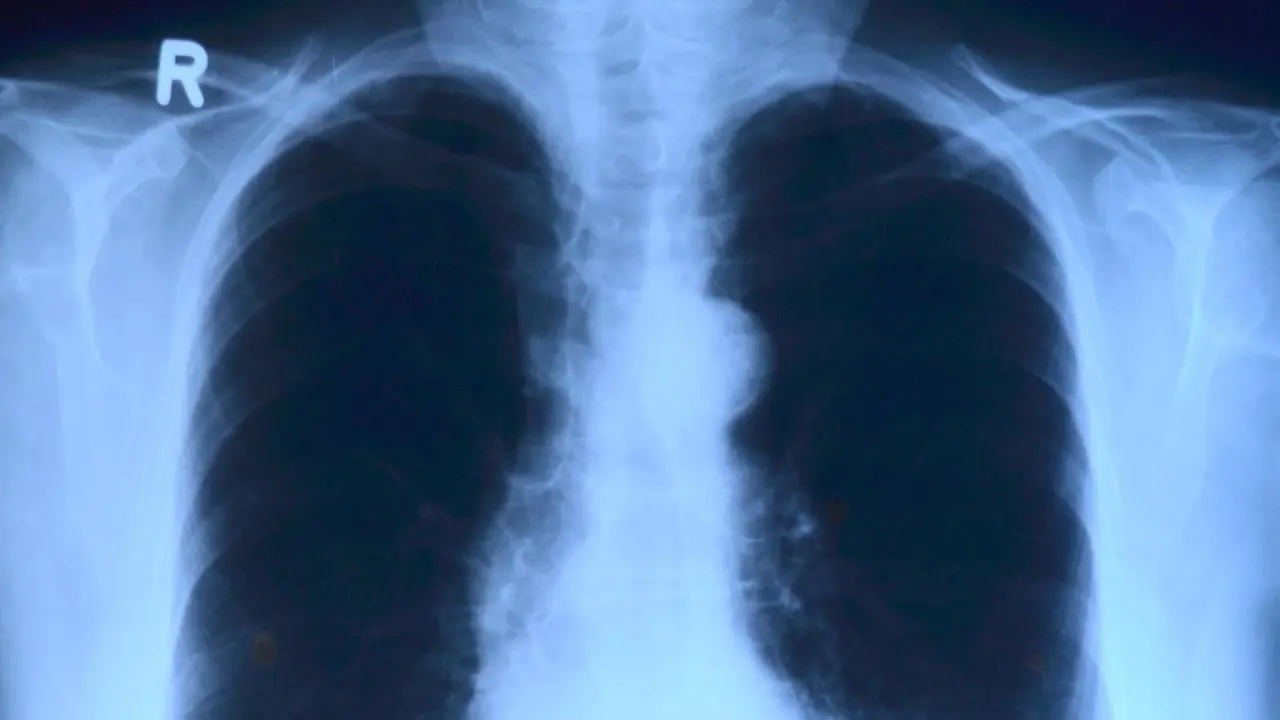

Akciğer kanseri, bu organda bulunan hücrelerin normal olmayan bir şekilde çoğalması ve farklı bir dokuyu (tümör) meydana getirmesidir. Oluşan bu tümörler, akciğerin fonksiyonlarını yerine getirmesine engel olur. Ayrıca diğer organlara da sıçrayabilir ve benzer etkileri o organlarda da gösterebilir.

Akciğer cerrahisi, akciğer kanserinin tedavisi için kullanılan yöntemlerden biridir. Birçok kanser türünde olduğu gibi burada da tümörlerin oluşma olasılığı vardır ve bu tümörler kısa sürede büyük boyutlara ulaşabilmektedir. Böyle durumlarda ilk olarak akciğer cerrahisi yöntemleri ile tümörlerin temizlenmesi gerekir.